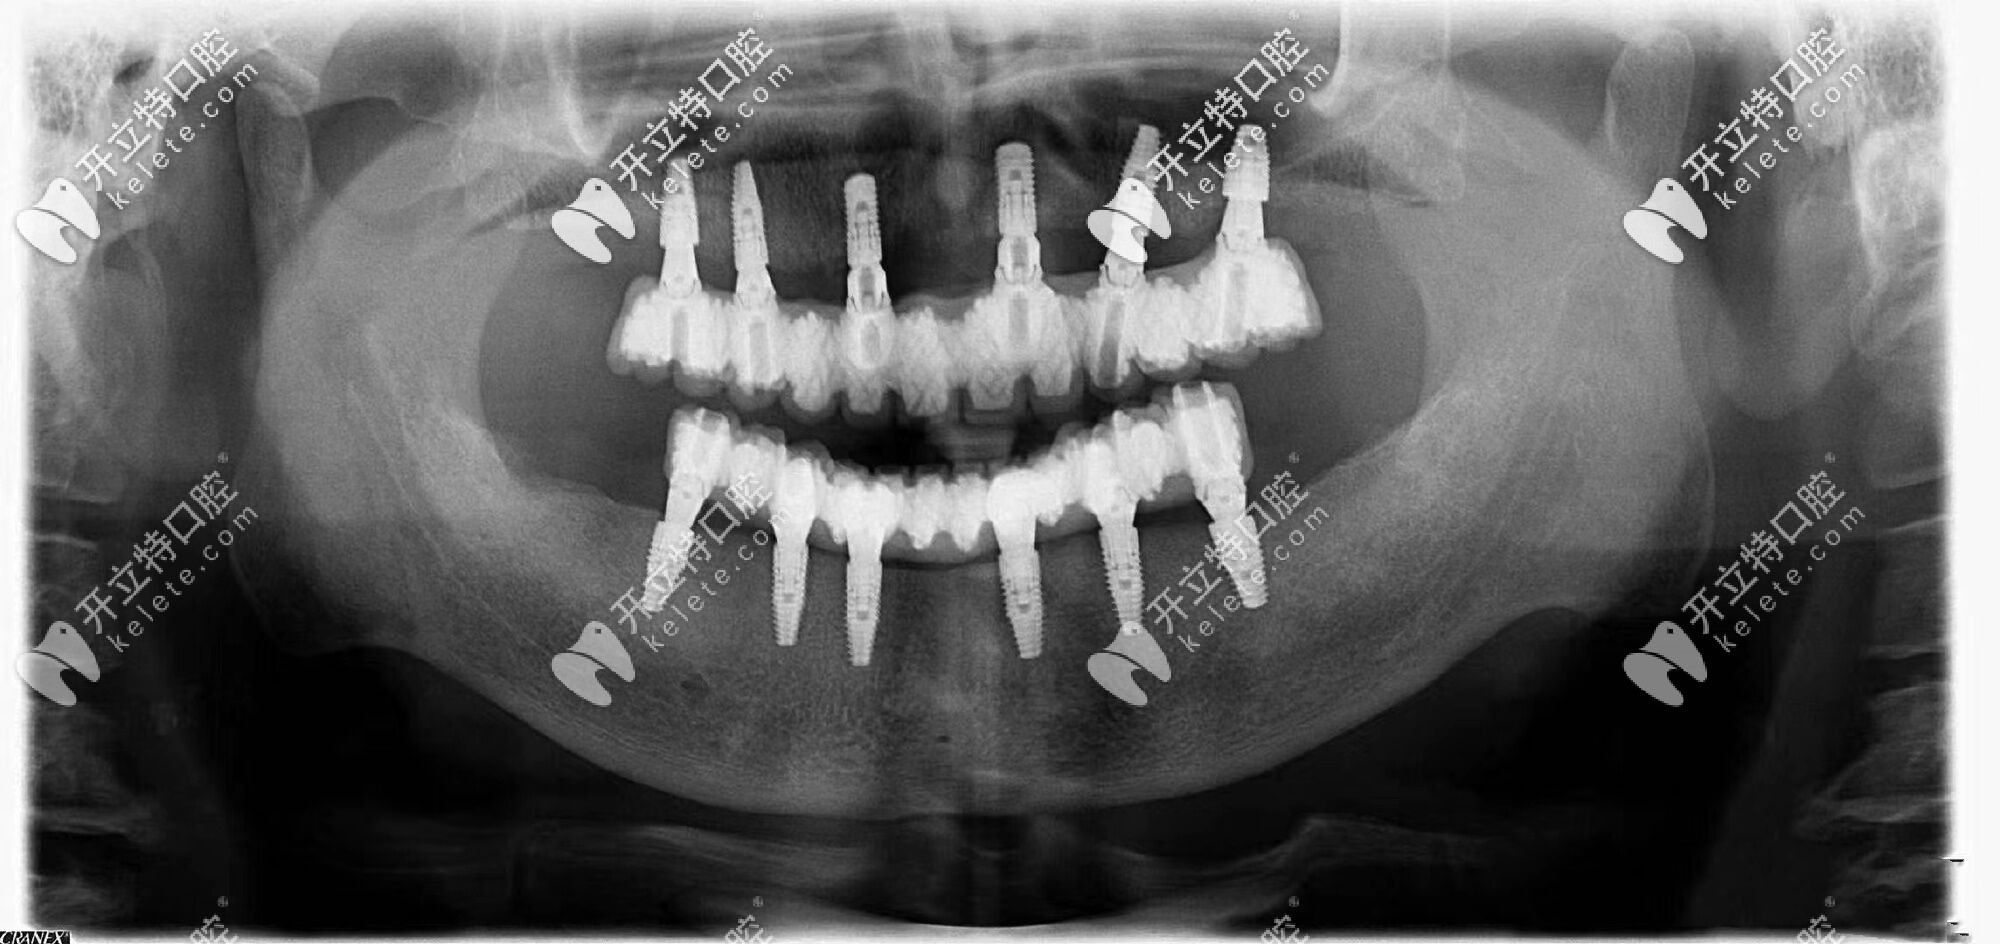

由于常年戴活動假牙,導(dǎo)致自身牙槽骨的條件較差,醫(yī)生給張叔設(shè)計了全口即刻種植牙的方案,沒想到3個小時左右的時間就完成了種植牙,并且真的是當天種牙,當天吃飯啊!

沈陽歡樂仁愛口腔的即刻修復(fù),讓張叔沒有無牙的空窗期,不僅恢復(fù)了咀嚼進食功能,更保證了發(fā)音和美觀,大幅度提升了晚年的幸福指數(shù)。